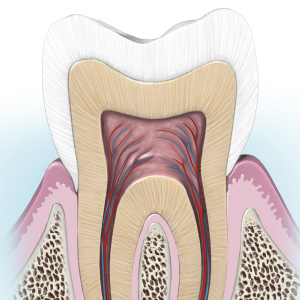

Developments in Endodontics

Wednesday, July 14, 2021

This Compendium eBook offers a continuing education (CE) article on mineral trioxide aggregate (MTA) and its composition, clinical applications, and research findings. This eBook also includes a case report on the use of conebeam computed tomography (CBCT) to diagnose anatomical disparities...